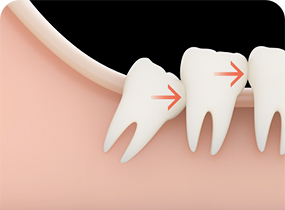

CASE 02

사랑니가 어금니를

앞쪽으로 미는 경우 -